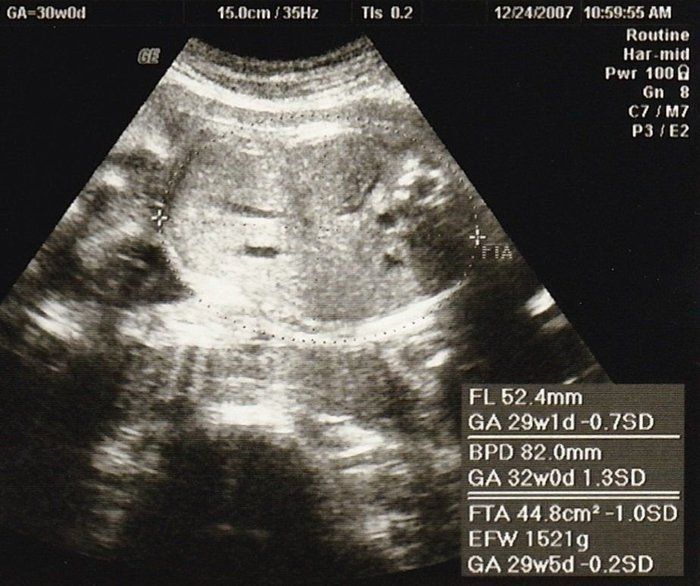

こぢんまり子さんの妊娠30週目のエコー写真 赤ちゃんの体重が少なめだと指摘される

エコーは左下の曲線が頭、真ん中の白っぽいのが手です。おなかの中で、よくしゃっくりをする赤ちゃんでした。しゃっくりをしているときにおなかに触ると、びくっとしているのが分かるので、夫にも触ってもらい、2人で「元気だね」と喜びました。

検診ではエコーで赤ちゃんの太ももの長さと頭の長さを計測して、推定体重を教えてもらっていたのですが、この頃から赤ちゃんの体重が少なめだと医師に言われるようになりました。